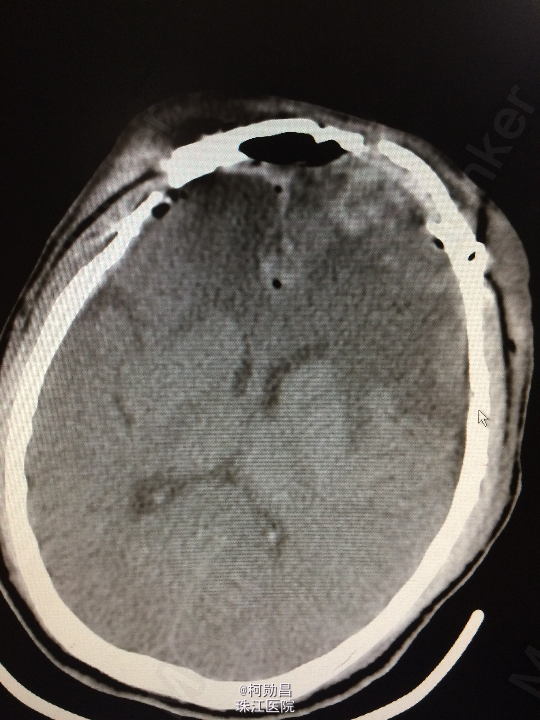

主诉:头痛伴左眼视力下降半年 病史:患者46岁男性,缘于半年前无明显诱因出现头痛,当时未予特殊处理,后症状进行性加重,并发左眼视力下降,于当地医院行头颅CT及MR检查提示颅内占位,为进一步治疗而入我院。 既往病史:5年前曾患鼻咽癌

查体:神志清楚,对答流利,左侧眼裂变小,左侧瞳孔散大,直径4mm,对光反射迟钝,左眼视力下降。右侧正常。 辅助检查:头颅MR提示前颅底筛沟通病变

诊断:鼻咽癌脑转移 处理:全麻下行颅筛沟通占位切除术,术后病理提示:鼻咽非角化鼻咽癌脑转移